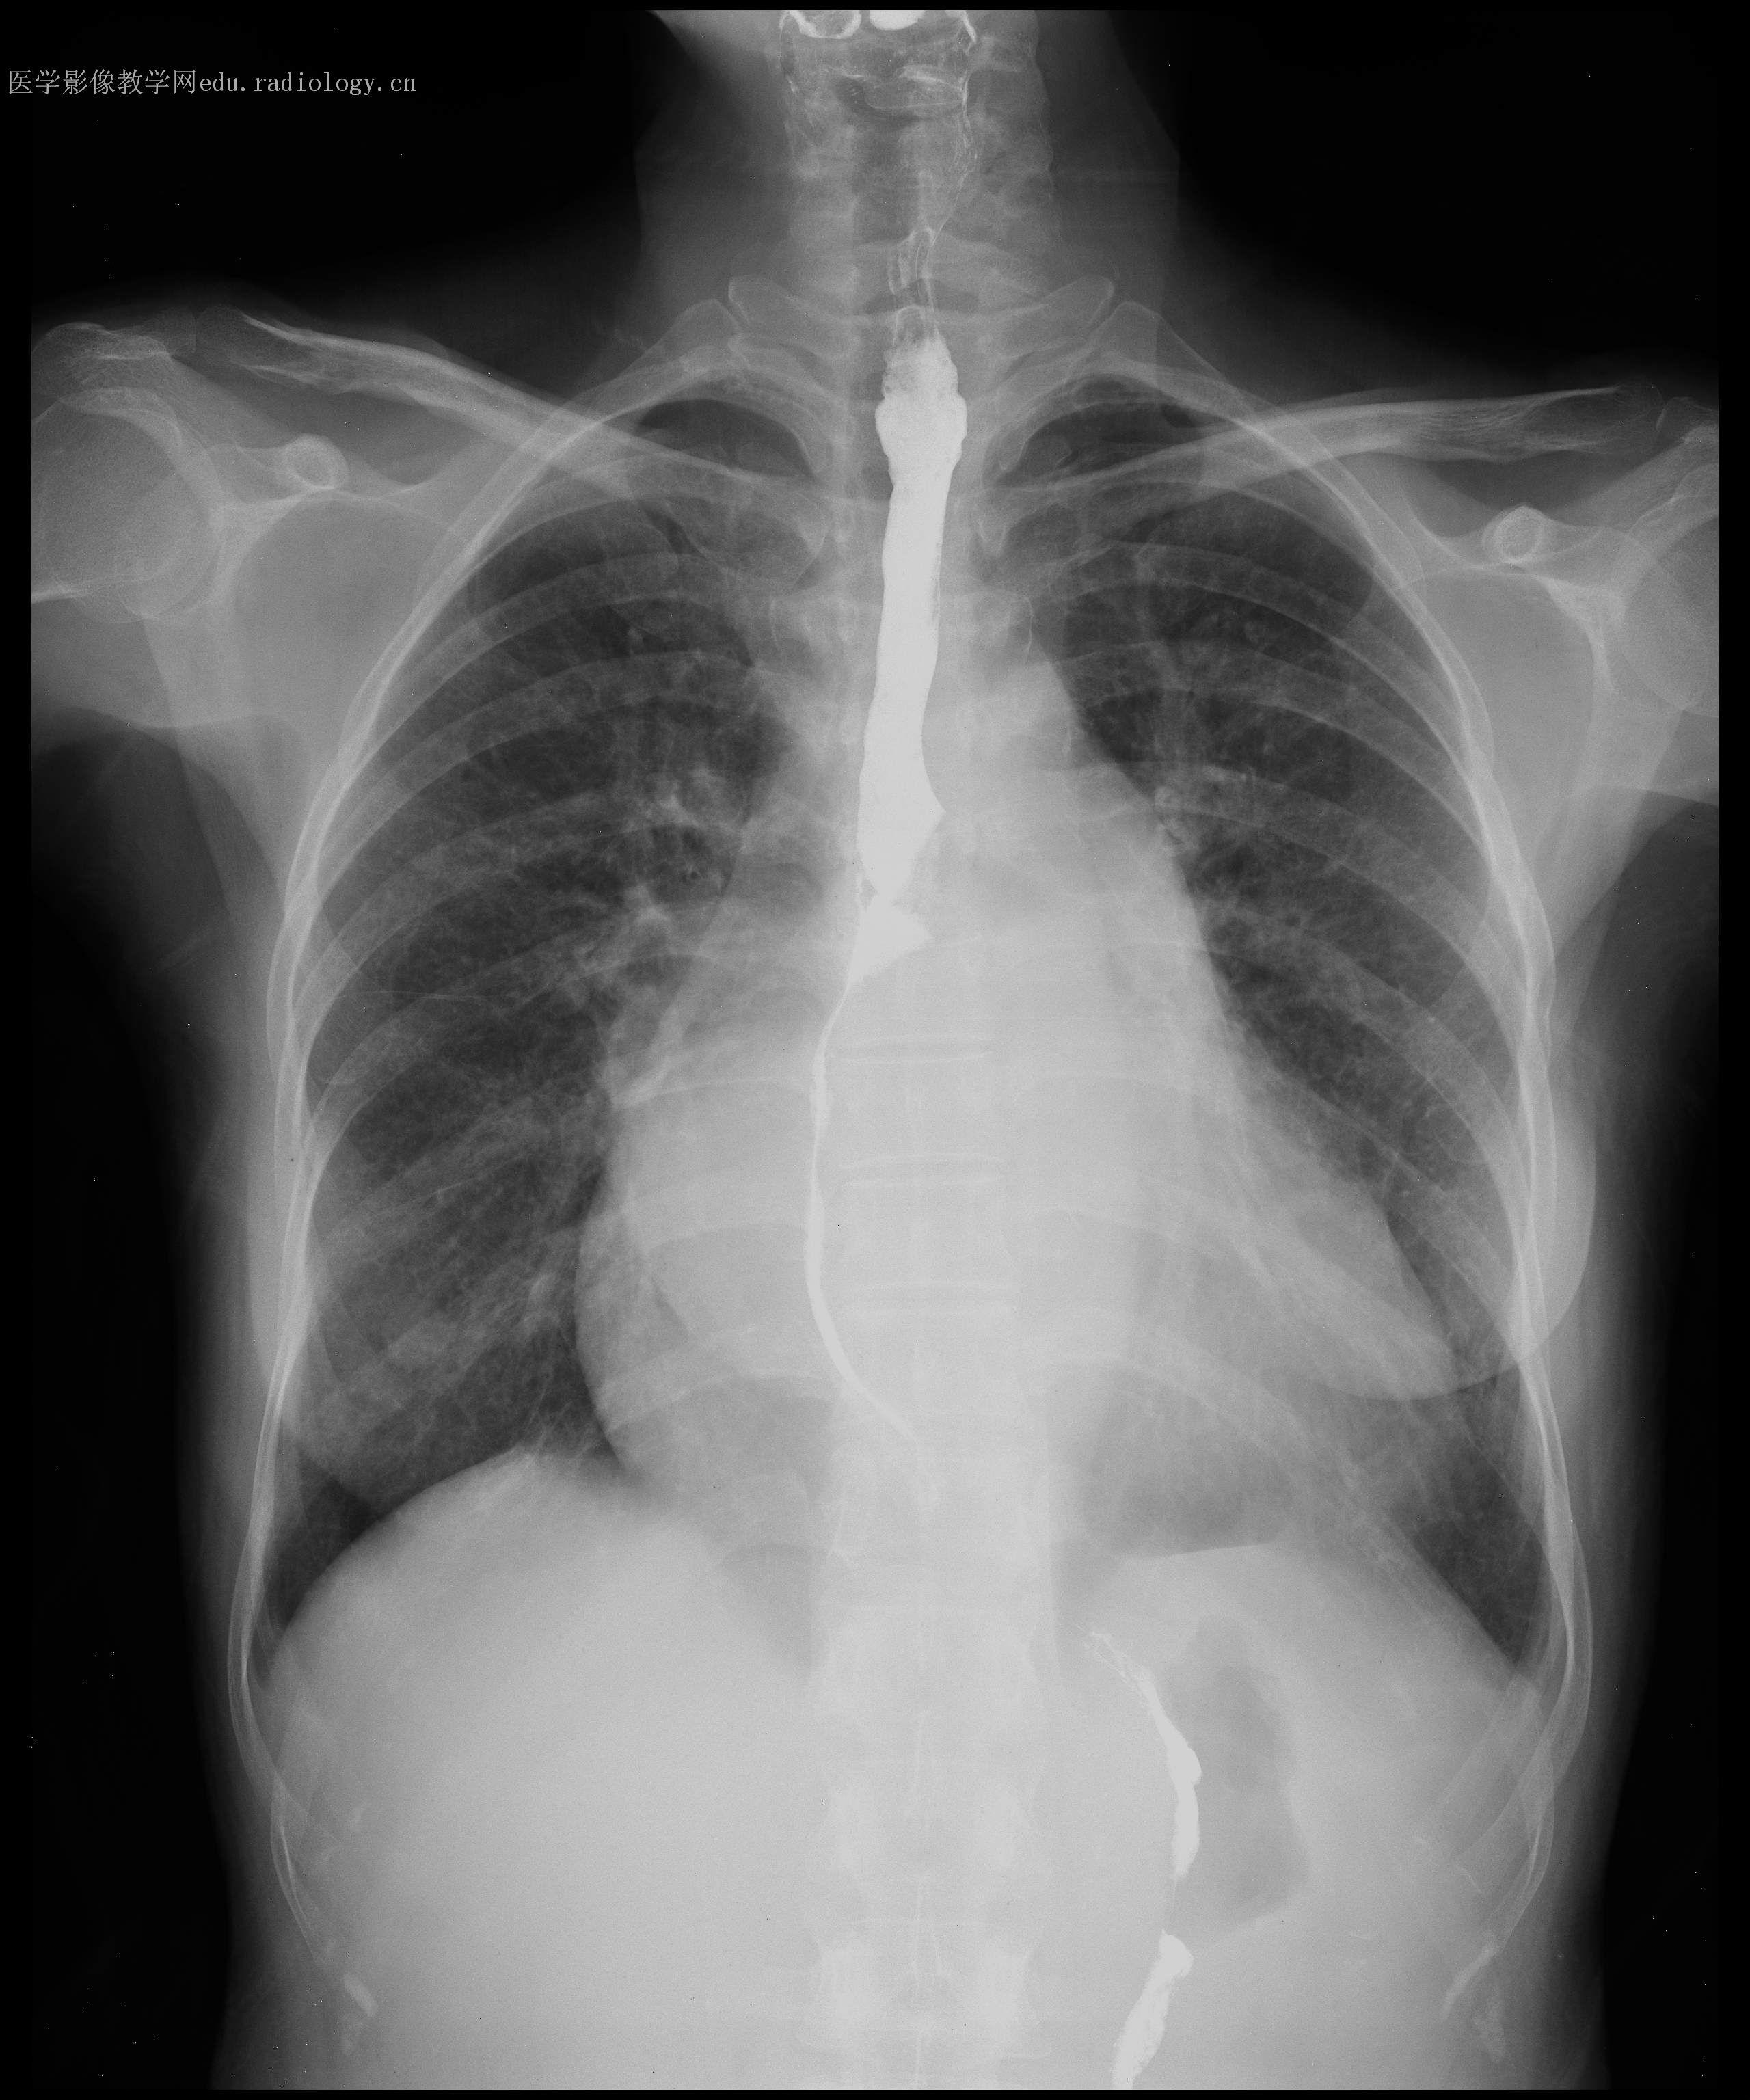

风湿性心脏病是由风湿热反复发作导致心脏瓣膜受损,进而引发瓣膜增厚纤维化狭窄或关闭不全,最终造成心脏功能异常的一种疾病,患者常出现胸闷气喘心脏变大变肥厚等症状具体介绍如下病因风湿性心脏病的主要病因是风湿热反复发作风湿热是一种与A组乙型溶血性链球菌感染有关的自身免疫性疾病;1 心力衰竭相关症状风湿性心脏病的核心病理是瓣膜关闭不全穿孔或缺损,导致心脏泵血功能异常,进而引发心力衰竭典型表现为活动后气喘,患者在进行轻度体力活动如爬楼梯快走时即出现呼吸急促,休息后可缓解随着病情进展,静息状态下也可能出现呼吸困难,甚至夜间阵发性呼吸困难需坐起呼吸2;皮肤病变部分患者可能出现环形红斑,表现为皮肤上出现圆形或椭圆形红斑,中央区域颜色较浅皮肤病变通常在发热后出现,但也可能早于发热,需注意观察心脏杂音是风湿性心脏病前期的重要症状,由心脏瓣膜受损引起杂音通常在胸骨左缘第3肋间听到,呈吹风样,提示可能存在瓣膜狭窄或关闭不全其他症状;风湿性心脏病的症状主要包括以下几类一心脏功能相关症状风湿性心脏病的核心病理改变是心肌及瓣膜受损如瓣膜关闭不全穿孔或缺损,导致心脏泵血功能异常患者常出现活动后气喘,尤其在运动爬楼梯或情绪激动时加重,休息后可缓解这是由于心脏代偿性收缩增强,但瓣膜病变导致血液反流或输出受阻;风湿性心脏病的症状表现多样,具体如下一早期症状1呼吸困难心脏瓣膜病变导致肺部淤血,影响气体交换患者可能在体力活动情绪激动或平躺时出现呼吸急促气短儿童表现为活动耐力下降,老年人症状易被忽视,慢性肺部疾病患者需鉴别诊断2乏力心脏功能下降导致组织器官供血供氧不足患者日常活动后易疲倦,体力劳动者工作。

风湿性心脏病的症状因心脏瓣膜病变程度和类型不同而有所差异,主要症状如下一二尖瓣狭窄相关症状 呼吸困难最常见,早期为劳力性呼吸困难,随病情进展可出现静息时呼吸困难端坐呼吸,甚至夜间阵发性呼吸困难咯血表现为痰中带血或大咯血咳嗽多为干咳,可伴声音嘶哑心悸心跳加快,房颤时;风湿性心脏病的症状因累及瓣膜的不同而有所差异二尖瓣受累时最常见的症状是劳力性呼吸困难,即患者在体力活动后出现呼吸急促困难,休息后缓解随着病情进展,可出现喘憋,尤其在夜间平卧时加重,导致夜里不能平卧,需坐起或半卧位才能缓解,这是由于肺淤血肺水肿所致患者还常伴有咳嗽咳痰,痰;一早期隐匿性表现疾病初期患者通常无明显症状,或仅在剧烈运动后出现轻微不适这是由于瓣膜病变处于代偿期,心脏可通过增大心肌收缩力维持正常功能,但此时若进行心脏超声检查,可能已发现瓣膜增厚粘连或钙化等结构性改变二典型瓣膜功能障碍症状风湿性心脏病主要累及二尖瓣三尖瓣和主动脉瓣,导致。

呼吸困难是风湿性心脏病的常见症状,主要由左心衰竭引发患者常在体力活动后夜间睡眠中或清晨起床时出现呼吸急促,严重时需端坐呼吸以缓解症状咳嗽多为干咳,可能伴有少量白色痰液,尤其在睡眠或活动后加重其机制与肺部淤血或支气管黏膜受刺激有关,长期可发展为慢性咳嗽咯血表现为痰中带血或血痰;女性在妊娠等特殊生理状态下,心脏负担增加,会使呼吸困难症状更为突出,且可能影响呼吸功能的代偿能力乏力患者会感到全身疲倦没有力气,这是因为心脏功能受损,心输出量减少,全身组织器官供血不足,能量代谢障碍儿童处于生长发育阶段,若患有风湿性心脏病出现乏力,会影响其生长发育和活动能力老年;心悸患者自觉心跳异常过快过慢或不规则,可伴胸闷乏力,心电图检查常显示心律失常如房颤需强调的是,风湿性心脏病的症状具有渐进性,早期可能仅表现为轻微乏力或活动后气促,易被忽视若出现上述组合症状如咳嗽+呼吸困难+心悸,或原有风湿热病史者突发心功能不全,应立即进行心脏。